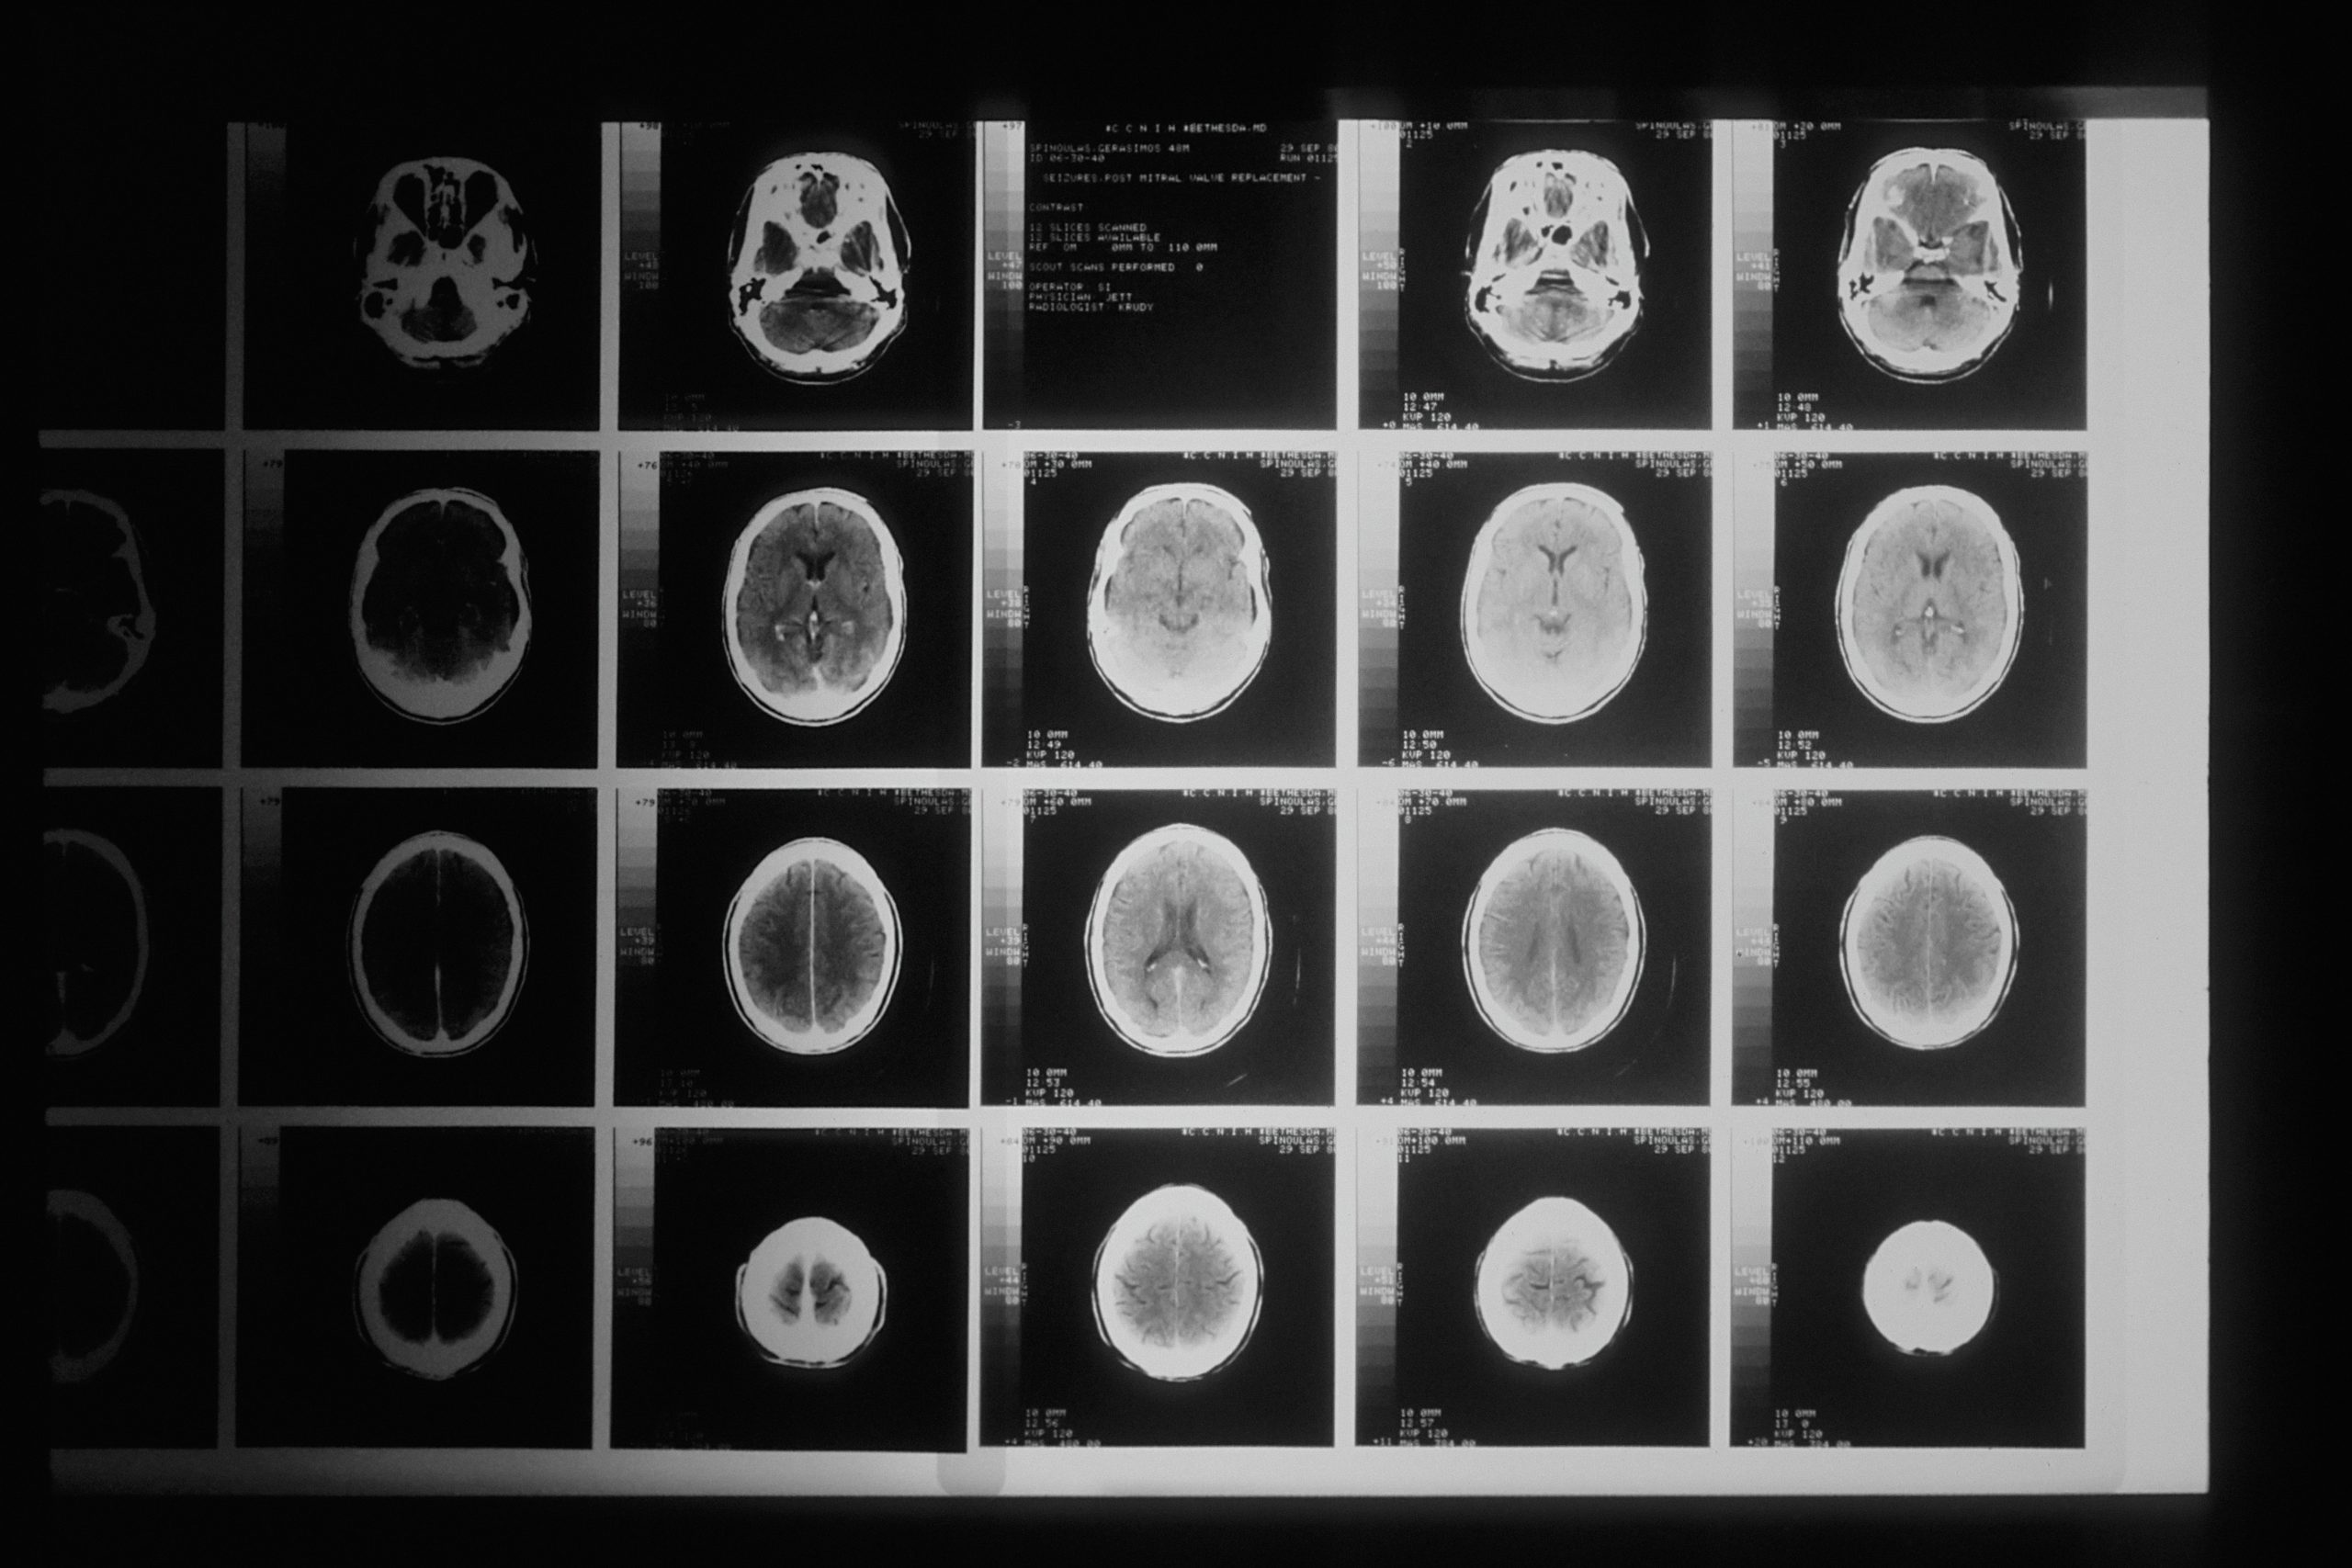

Nuestro cerebro nos define, procesa el mundo que nos rodea y determina como respondemos a los estímulos. La neurociencia es la disciplina que trabaja para comprender la estructura y funcionamiento del sistema nervioso y que está en plena revolución gracias a:  colaboración entre disciplinas científicas, y la aplicación de nuevas tecnologías que están facilitando la observación minuciosa del cerebro y nuevas aplicaciones de interfaces cerebro-máquinas.

Actualmente la neurociencia está trabajando en 3 grandes áreas:

• Más allá del cerebro, focalizándose en las funciones del sistema nervioso,

• Conexiones neuronales, estudiando cómo funcionan las neuronas y sus conexiones.

• Salud mental, estudiando las disfunciones del sistema nervioso que provocan las enfermedades mentales.